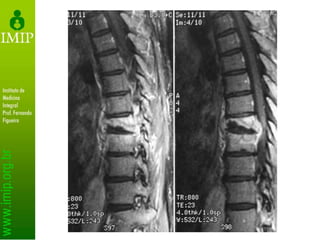

Exames secundários

• RNM

– Determina extensão da infecção

– Identifica tecidos acometidos

– Não identifica etiologia

• Não exclui biópsia

• RNM facilita a distinção entre tuberculose

e tumor

– Presença de abscesso e fragmentos ósseos